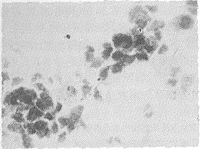

2.1 涂片检查 经改良S法处理的痰标本涂片中癌细胞形态完整,含杂质少,易于辨认(图1~3)。常规涂片检查发现肺癌细胞或高度可疑肺癌细胞者共35例,占28%(35/125),改良S法收集并处理痰标本后涂片查出癌细胞或高度可疑癌细胞者共69例,占55.2%(69/125)。经χ2检验,两组间阳性率的差异有显著性(P<0.01)。改良S法检测到的69例痰细胞学阳性患者中,能明确病理类型者58例(鳞癌28例,腺癌9例,小细胞肺癌21例)。常规法检测到的35例中,明确病理类型者26例(鳞癌13例,腺癌5例,小细胞肺癌8例)。两组间病理类型确诊率的差异也有显著性(P<0.01)。改良S法的阳性检出率与肿瘤的组织病理类型、TNM分期及肿瘤在支气管内的位置有明显关系(表1)。

图1 腺癌细胞:细胞排列紧密,为腺样排列,胞浆内有多个空泡。细胞核浆比例大,细胞核靠边,呈卵圆形,核膜核仁明显。HE×400

Fig 1 Adenocarcinoma cell: the cells arranged compactly and acinously with many vacuoles seen in cytoplasm. The high nucleocytoplasmic ratio, marginal oval nucleus with nuclear membrane and nucleoli was discerned clearly in each cell.